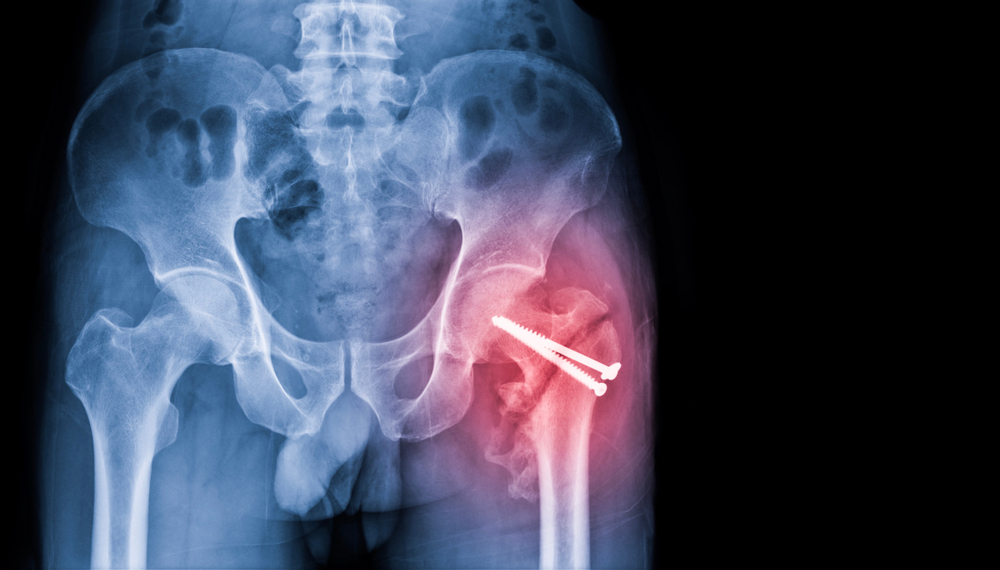

ការបាក់ក្បាលឆ្អឹងភ្លៅ ឬកឆ្អឹងភ្លៅគឺជាការបាក់ឆ្អឹងនៅតំបន់ភ្លៅ (femur) ដែលស្ថិតនៅត្រគាក។ សន្លាក់ឆ្អឹងត្រគាកមានរូបរាងដូចគ្រាប់បាល់នៅក្បាលរបស់ឆ្អឹង និងប្រឡង់របស់វា។ ការបាក់នៅករបស់ឆ្អឹងភ្លៅគឺបាក់នៅក្រោមក្បាលឆ្អឹងដែលមានរាងមូលដូចបាល់នោះ។ ការបាក់ឆ្អឹងភ្លៅដែលមានដាច់សរសៃឈាម ជាធម្មតាគឺមានបញ្ហាក្នុងការព្យាបាល តែភាគច្រើនអាចជាសះស្បើយវិញបានក្រោយពីការវះកាត់។

ជាទូទៅគ្រូពេទ្យធ្វើរោគវិនិច្ឆ័យដោយការពិនិត្យលើរាងកាយ។ ក្នុងករណីដែលឃើញរោគសញ្ញាមិនច្បាស់ ឬងាយយល់ច្រឡំនឹងជំងឺដទៃទៀតគ្រូពេទ្យនឹងធ្វើការថតកាំរស្មី X ដើម្បីបញ្ជាក់ពីកន្លែងដែលឆ្អឹងបានបាក់។

ការព្យាបាលគឺតម្រូវឲ្យធ្វើការវះកាត់។ ការវះកាត់ដោយដាក់រណបនៅកន្លែងដែលបាក់ ឬដាក់វីស និងបន្ទះទប់ឆ្អឹងដើម្បីប្រមូលផ្តុំបំណែកឆ្អឹងឲ្យចូលគ្នាវិញ។ ការវះកាត់មូយផ្សេងទៀតគឺការដាក់ឆ្អឹងសប្បនិមិត្ត នៅក្បាលឆ្អឹងតែមួយ ឬទាំងក្បាលឆ្អឹងនិងប្រហោងក្បាលឆ្អឹង។ ពេលខ្លះការវះកាត់មិនអាចធ្វើឱ្យសន្លាក់មានសភាពល្អឡើងវិញបាន ក៏មកពីឆ្អឹងដែលនៅសល់គឺស្តើងពេក។ចំពោះអ្នកជំងឺដែលមានជំងឺធ្ងន់ធ្ងរ ការព្យាបាលគឺសម្រាកនៅលើគ្រែដើម្បីឱ្យឆ្អឹងដែលបាក់អាចជាប់គ្នាវិញ។